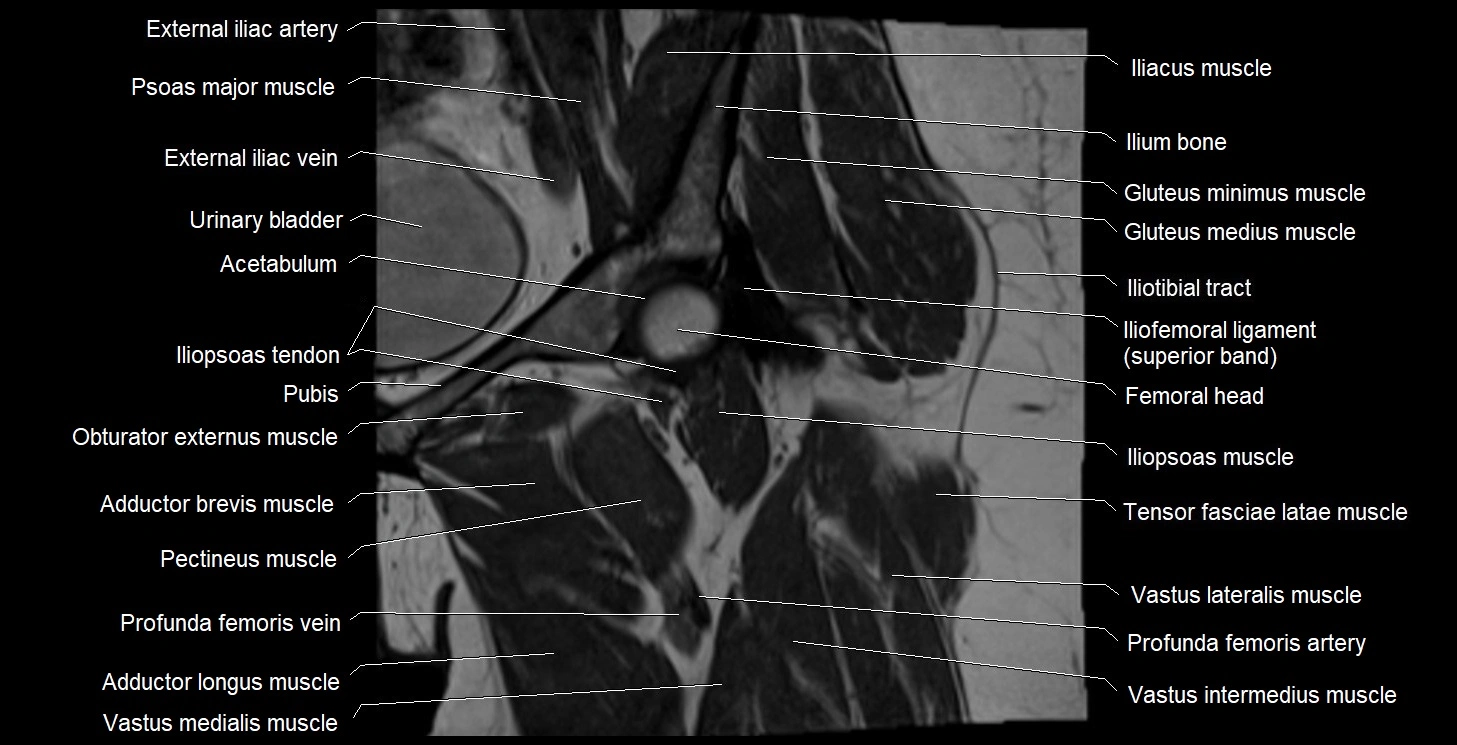

- Acetabulum

- Adductor brevis muscle

- Adductor longus muscle

- Deep femoral vein (profunda femoris vein)

- External iliac artery

- External iliac vein

- Femoral vein

- Gluteus minimus muscle

- Head of femur

- Iliofemoral Ligament superior band (transverse band, lateral band)

- Iliofemoral ligament

- Iliopsoas muscle

- Iliopsoas tendon

- Iliotibial tract

- Ilium bone

- Obturator externus muscle

- Pectineus muscle

- Psoas major muscle

- Tensor fasciae latae muscle

- Urinary bladder

- Vastus intermedius muscle

- Vastus lateralis muscle

- Vastus medialis muscle